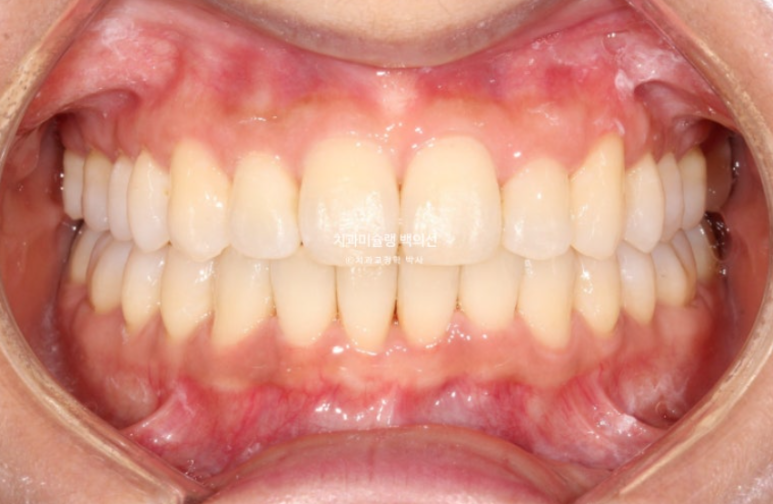

25.08

총 치료기간은 1년이고 재제작은 1회 했습니다.

교정치료의 완성은 예쁜 앞니와 어금니 교합입니다.

물샐틈 없는 교합이 되지 않으면 치료를 마무리 짓지 않습니다.